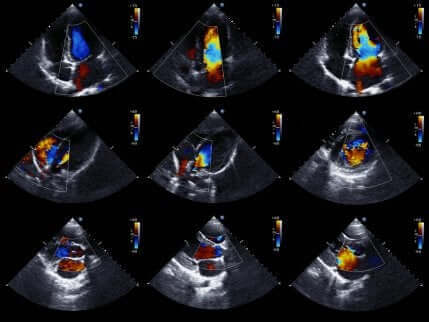

Sydämen ultraäänitutkimus

Sydämen ultraäänitutkimuksen avulla lääkintähenkilökunta pystyy tutkimaan potilaan sydäntä hyvin tarkasti.

Sydämen ultraäänitutkimus on erittäin suosittu menetelmä potilaan tutkimiseksi, sillä sen avulla saadaan otettua kuvia sydämestä liikkeessä. Siten sen kautta voidaan arvioida sydämen kammioiden terveyttä sekä niiden liikettä, jotta voidaan olla varmoja iskemian läsnäolosta tai sen puuttumisesta.

Lisäksi tällä menetelmällä voidaan arvioida sydämen kokoa ja vahvuuutta, kuten myös sen seinämien kuntoa. Yleisesti ottaen kyseessä on ei-invasiivinen menetelmä, joka ei tuota potilaalle mitään riskiä, sillä siinä hyödynnetään ultraäänitekniikkaa, jotta saadaan aikaan kuvia sydämestä.